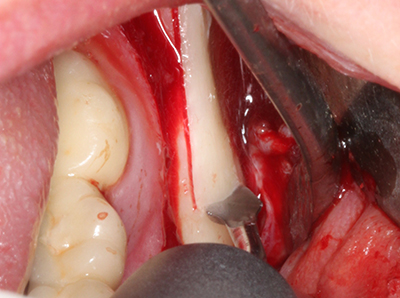

Knochengewebe ist nicht nur rein mineralisch, sondern auch in wesentlichen Anteilen aus Kollagenfasern aufgebaut. Dies gewährleistet neben einer guten Druckfestigkeit eine gewisse Flexibilität, welche für die Durchführung von Augmentationen genutzt werden kann. Bei der klassischen Expansionsplastik im Sinne eines Bone Splittings wird der atrophierte Kieferkamm in seiner Längsachse gespalten und nach Erreichen einer ausreichenden Osteotomietiefe vorsichtig aufgedehnt (Abb. 13-16), idealerweise ohne den Kiefer wesentlich zu deperiostieren (Brugnami, Caiazzo et al. 2014, Stricker, Fleiner et al. 2014). Bewährt haben sich Schrauben- und Plattensysteme mit zunehmender Expansionsdistanz, um die beiden Knochenlamellen unterhalb der Bruchschwelle voneinander zu distanzieren. In der Regel werden Restknochenbreiten von mindestens 3-4 mm gefordert (Chiapasco, Zaniboni et al. 2006), um eine ausreichende Flexibilität und knöcherne Bedeckung der einzubringenden Implantate zu gewährleisten. Ggf. kann eine ein- oder beidseitige vertikale Entlastungsosteotomie die Flexibilität verbessern. Als Alternative zur klassischen Technik wurde eine Kombination mit weiteren augmentativen Techniken vor allem auf der bukkalen Seite beschrieben.

Mittels Piezosägen erfolgt die Anlage des Splittings besonders schonend und ohne wesentliche Dimensionsverluste, so dass sich keine signifikanten Unterschiede von Implantaten im gesplitteten Kiefer im Vergleich zum nicht defizitären Alveolarkamm gezeigt haben (Chiapasco, Zaniboni et al. 2006, Danza, Guidi et al. 2009). Gerade beim lokal begrenzten und tiefen Splitting ist jedoch stets auf eine ausreichende Wasserkühlung zu achten, um thermische Belastungen in den apikalen Osteotomiebereichen zu vermeiden.